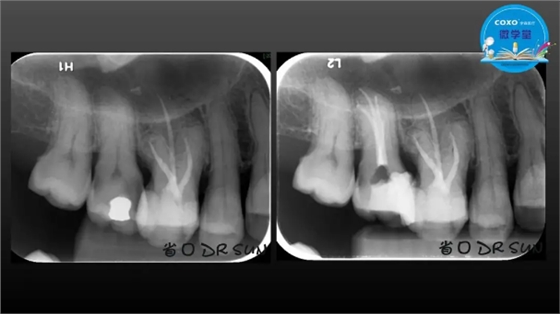

主任医师,牙体牙髓副主任, 广东省口腔医院牙体牙髓科 主任医师。2003年硕士研究生毕业,研究方向为牙体牙髓病学,擅长于牙体牙髓病的诊断、龋齿、牙髓炎、根尖周病的治疗以及前牙美容修复。